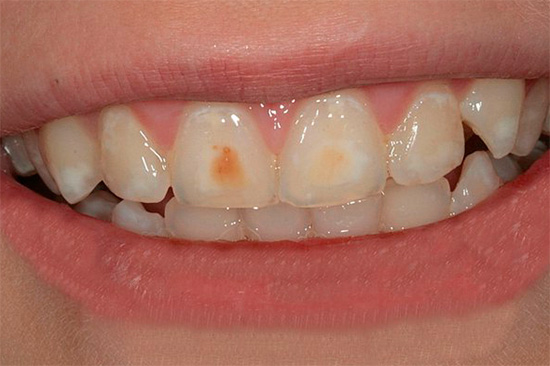

Un aspetto tipico dei denti con carie cronica è mostrato nella foto qui sotto:

Non ci sono lesioni estese dei denti e in alcuni punti le aree scure sono di dimensioni molto ridotte e spesso non attirano l'attenzione del paziente. Di solito il dolore è assente.

- La carie cronica nella fase spot quasi non si manifesta. Un dente può rispondere a cibi freddi o aria, ma questo non è percepito dal paziente come una patologia. L'area dello smalto demineralizzato appare come una macchia opaca biancastra sul dente.

- La carie superficiale cronica porta alla formazione di una cavità nello smalto dei denti, ma senza danni alla dentina. Tale cavità non ha bordi sporgenti, è ampia, ben aperta, lo smalto stesso di solito si scurisce a causa della pigmentazione, ma mantiene una durezza relativamente elevata.